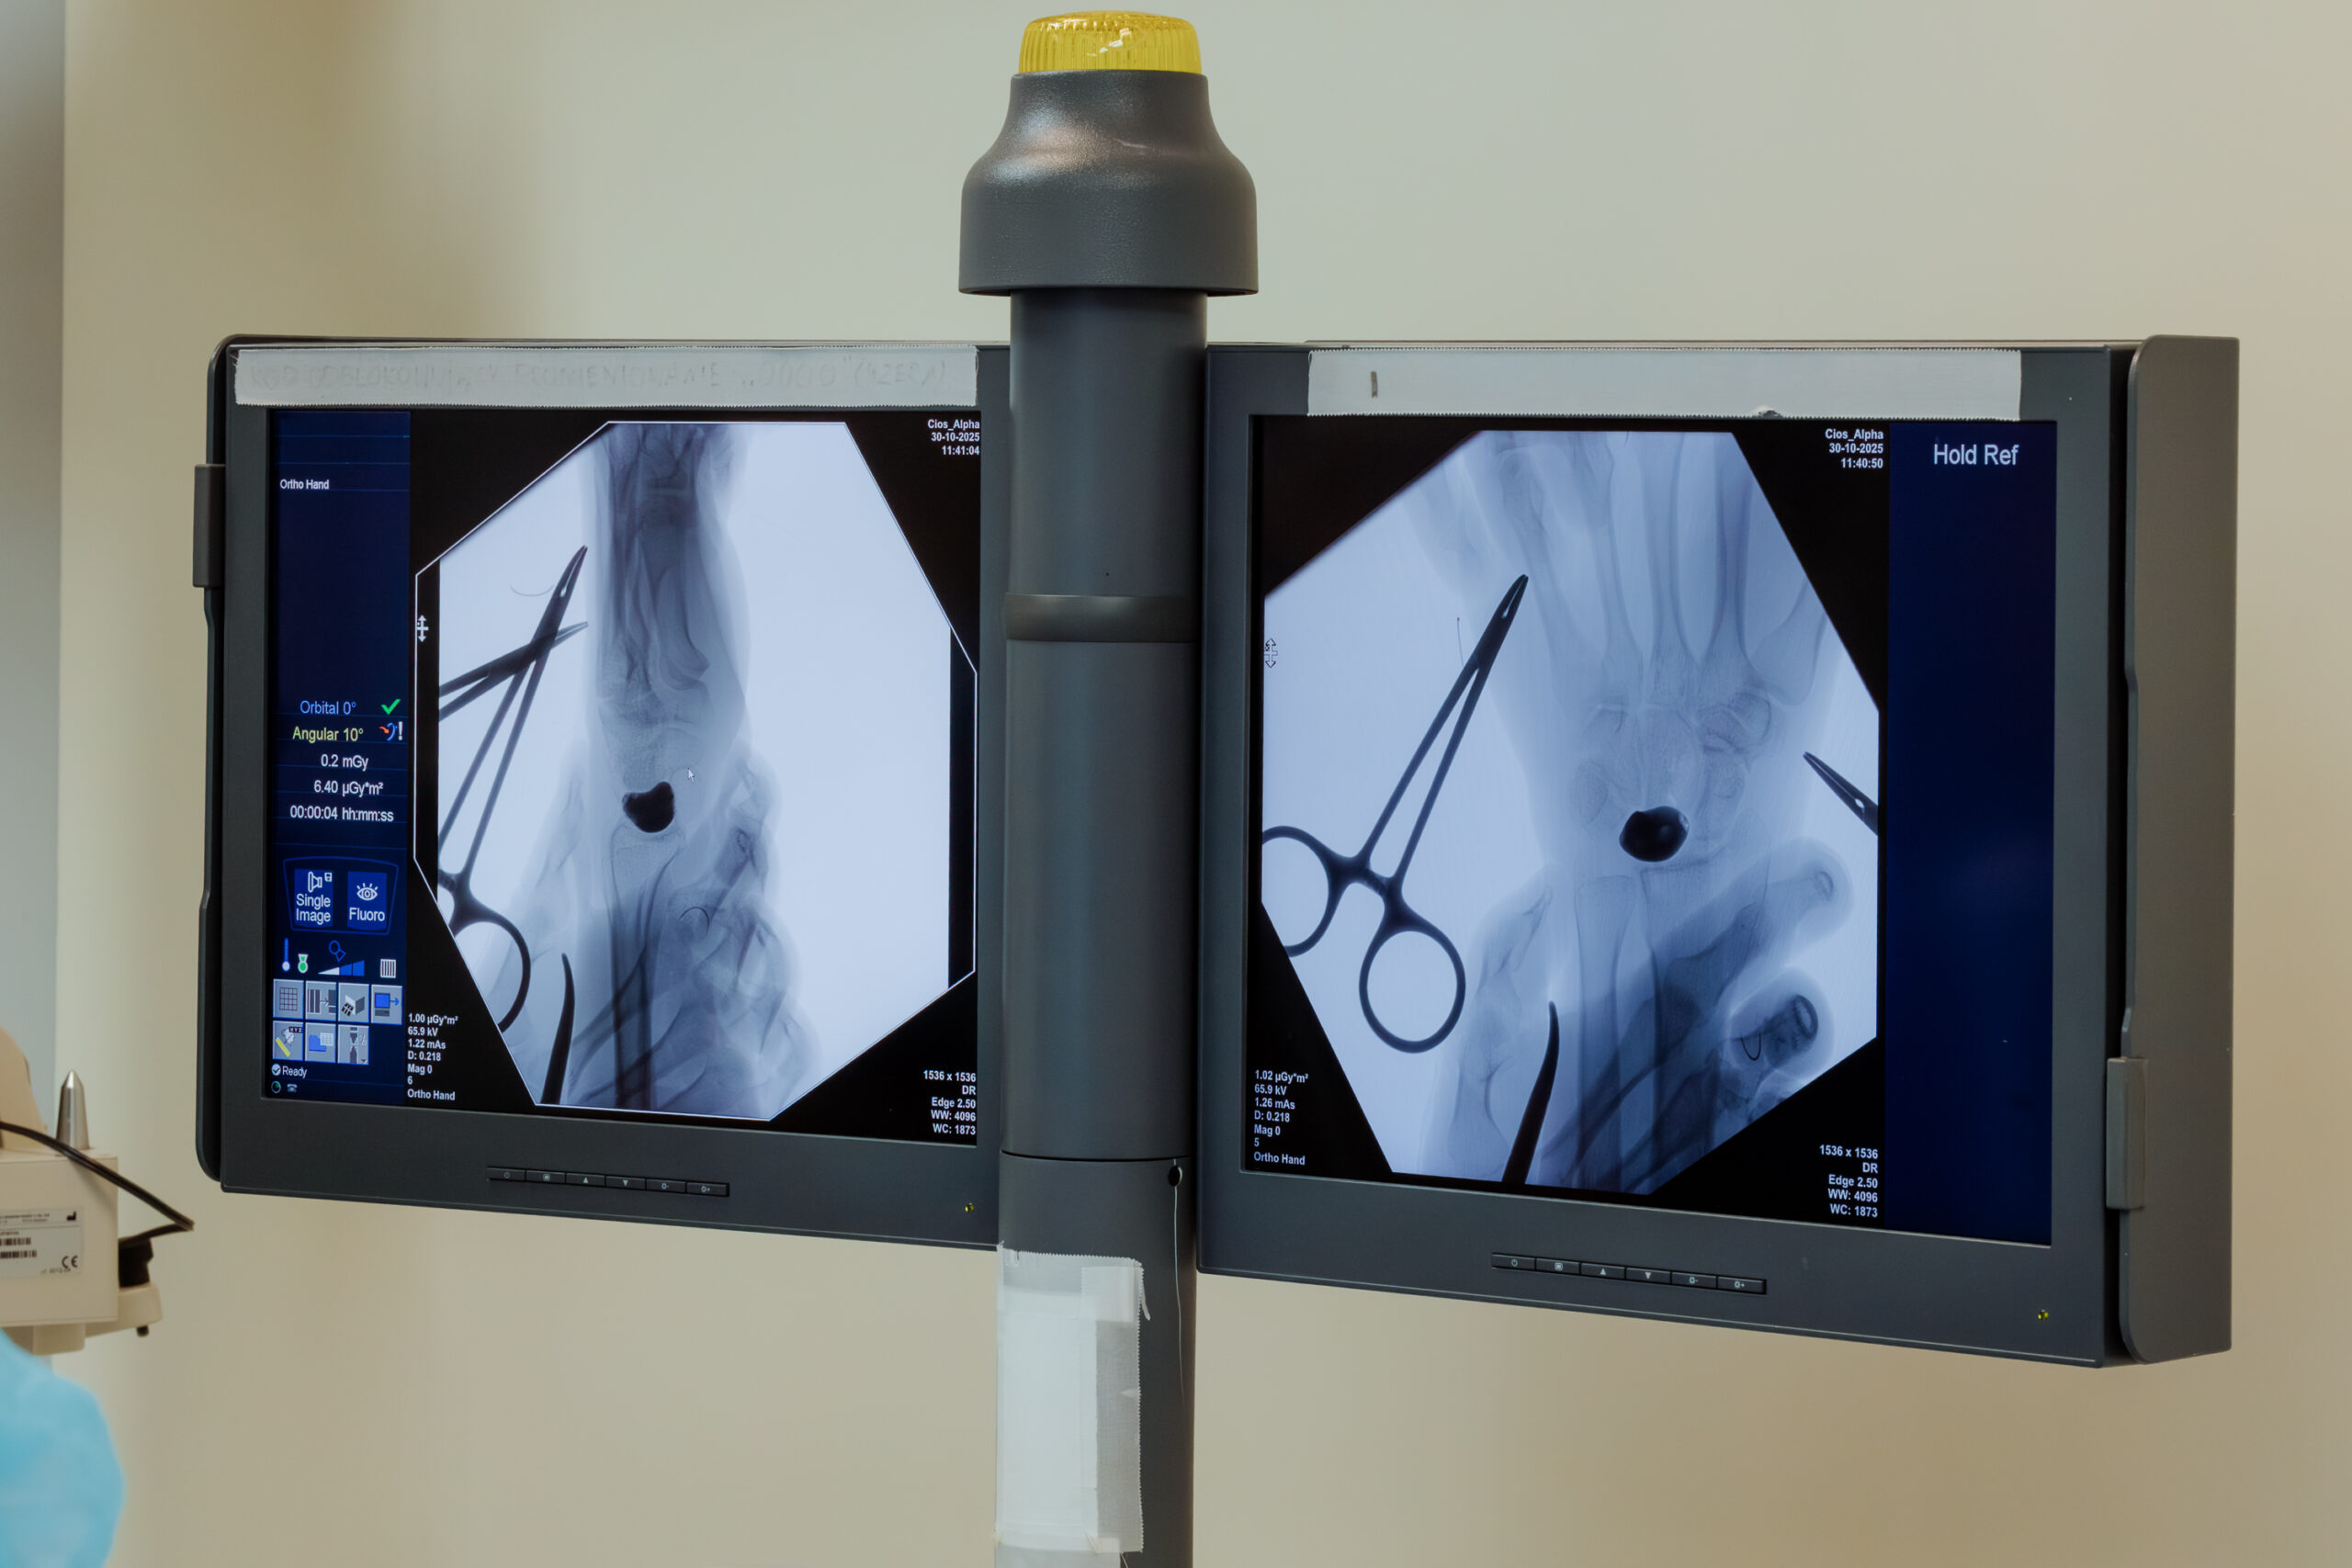

Przełom nastąpił dopiero w Lublinie, gdzie trafił do Klinicznego Oddziału Ortopedii i Traumatologii USK nr 4. To właśnie tutaj zespół pod kierownictwem dr. n. med. Piotra Piecha zdecydował się na nowatorską metodę – wszczepienie spersonalizowanego implantu kości wydrukowanego w technologii 3D.

Przygotowania do zabiegu trwały niemal rok. Na podstawie cyfrowego odwzorowania anatomii pacjenta stworzono implant „szyty na miarę”, wykonany z biokompatybilnego stopu tytanu. Jego kluczowe powierzchnie zostały wygładzone, a w miejscach wymagających większej odporności pokryte powłoką diamentopodobną DLC, która minimalizuje tarcie i zużycie.

– W tego typu operacjach o sukcesie decyduje nie tylko technologia, ale też precyzja chirurgiczna i plastyka tkanek miękkich. Odtworzenie struktur więzadłowych oraz kontrola ustawienia implantu są kluczowe dla zachowania funkcji nadgarstka – wyjaśnia dr Piech.